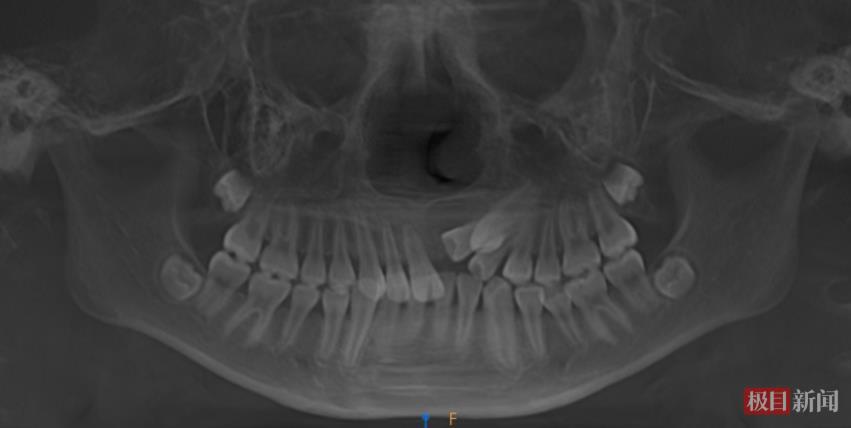

口腔正畸科副主任医师尹苗接诊后进行了细致检查,发现康康口内乳牙已全部脱落,进入恒牙列期,后续替换的乳牙均正常萌出,但左上颌区本应更早萌出的3颗前牙却“缺席”。通过锥形束CT(CBCT)检查,结果显示这3颗恒牙并非未发育,而是全部位置异常,牙冠呈近中倾斜阻生状态,其中左上门牙完全埋伏于颌骨内。

针对康康的情况,尹苗副主任医师团队制定了治疗方案:首先通过CBCT精准定位埋伏牙位置、角度及与邻牙关系;随后在可见牙列上安装托槽弓丝,以弹性链或钢丝连接并施加轻柔持续的牵引力,激活牙周反应,促使牙齿沿预设轨道移动至正常位置。牙齿归位后需经历稳定期,拆除矫治器后还需佩戴保持器防止复位。